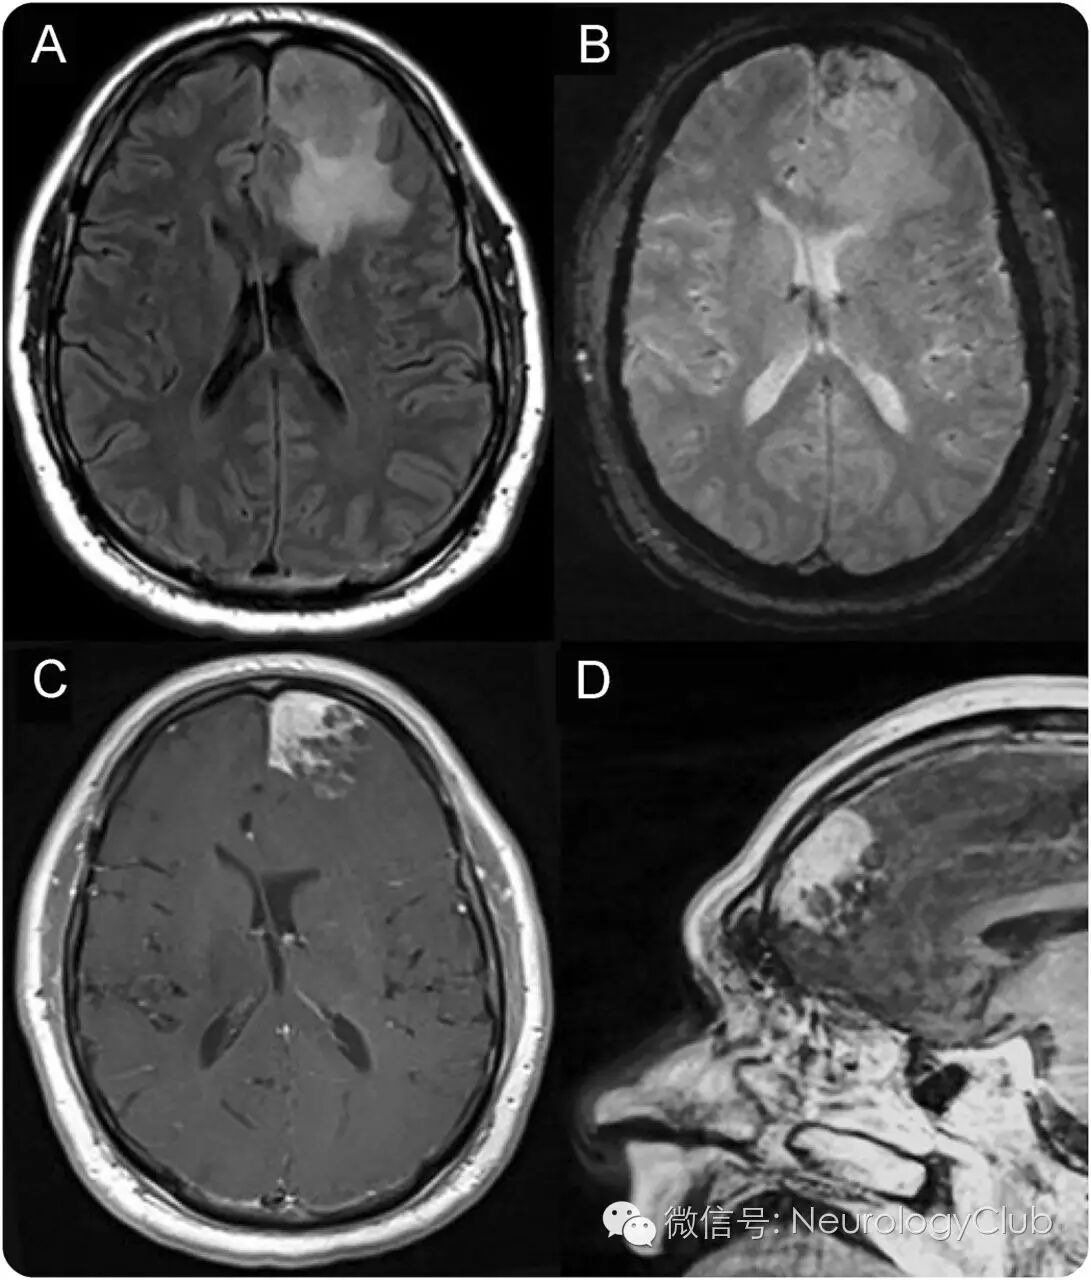

52岁男性,因机动车碰撞入院。查体提示格拉斯哥昏迷量表评分15分,右下肢轻瘫。CT平扫提示左侧额叶病灶。再行MRI可见左侧额上回肿块,怀疑高级别胶质瘤(图1)。

(图1:A:FLAIR可见左侧额叶肿块,边界浸润至脑内,伴血管源性水肿,压迫左侧脑室;B:T2*可见低信号,提示钙化,出血或两者兼有;C-D:T1增强可见肿瘤不均匀强化;未见脑膜瘤典型征象,如脑膜尾征或脑脊液分裂征)